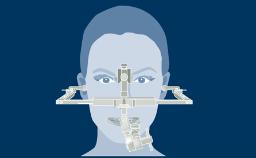

A implantodontia evoluiu consideravelmente desde os protocolos de tratamento precoce, nos quais o posicionamento dos implantes não era considerado crítico para um resultado bem-sucedido. Nesta abordagem orientada cirurgicamente, os implantes foram instalados onde havia osso suficiente para apoiá-los, e a ênfase estava no resultado funcional. Esta imagem clínica mostra três implantes adjacentes suportados por coroas unitárias. Isso proporcionou ao paciente um bom resultado funcional, mas a estética ao nível da emergência do implante foi apenas uma consideração secundária. Na implantodontia moderna, o resultado estético geral é de igual ou maior importância para o paciente. Os resultados estéticos estão intimamente relacionados a um alto nível de precisão no posicionamento dos implantes dentários de suporte. Uma segunda imagem clínica mostra um exemplo de uma coroa unitária implantossuportada no incisivo central superior esquerdo, onde o posicionamento cuidadoso do implante permitiu que o perfil de emergência imitasse o do incisivo central natural. Guias de transferência para orientar a instalação precisa tridimensional do implante são críticos para alcançar esse resultado. Este Módulo de Aprendizado ITI discutirá o uso rotineiro de guias de transferência na implantodontia.

- descrever o papel dos guias de transferência radiográficos e cirúrgicos

- discutir as vantagens e desvantagens dos vários tipos de guias de transferência